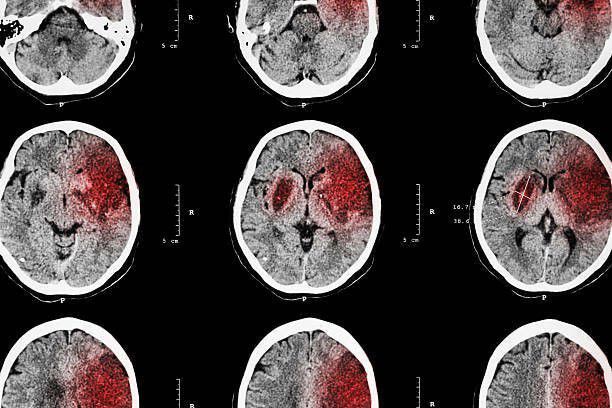

Ilustrasi pendarahan otak (rctiplus.com)